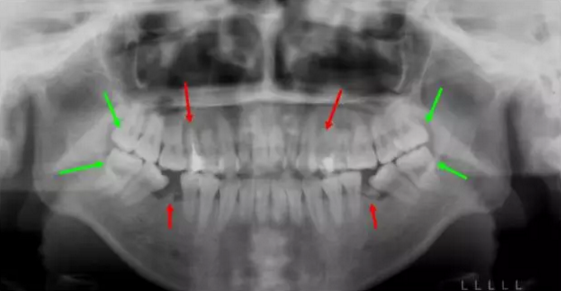

13.png

這個(gè)妹子正畸前,前牙不能咬合,牙凸又嘴凸而且還有殘余的牙根,牙列開(kāi)始傾斜。綜合考慮后,醫(yī)生拔除了箭頭所示8顆牙,沒(méi)有采取常規(guī)拔牙,因?yàn)樾枰M量拔除不能保留的病牙。